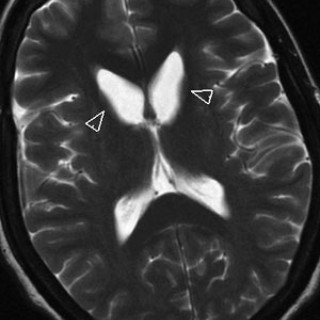

Sentrale venekatetre brukes rutinemessig i pasientbehandlingen ved norske sykehus. Den sentralvenøse tilgangen oppnås gjennom punksjon av v. jugularis interna, v. subclavia eller v. femoralis. Komplikasjoner knyttet til bruken ses både i forbindelse med selve innleggingen av kateteret, når kateteret er på plass og i bruk og når det skal fjernes. Komplikasjoner knyttet til innlegging av et sentralvenøst kateter er punksjon av nærliggende arterie, pneumothorax, arytmier, skade av plexus brachialis, skade på ductus thoracicus, luftembolisering og feilposisjonering av kateteret (1, 2)...